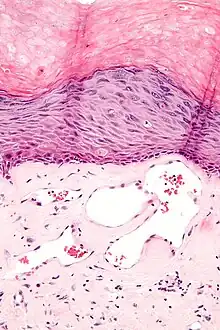

Angiokeratomas characteristically have large dilated blood vessels in the superficial dermis and hyperkeratosis (overlying the dilated vessels).

- Scrotal angiokeratoma (Fordyce type); dilated cavernous capillaries, acanthosis